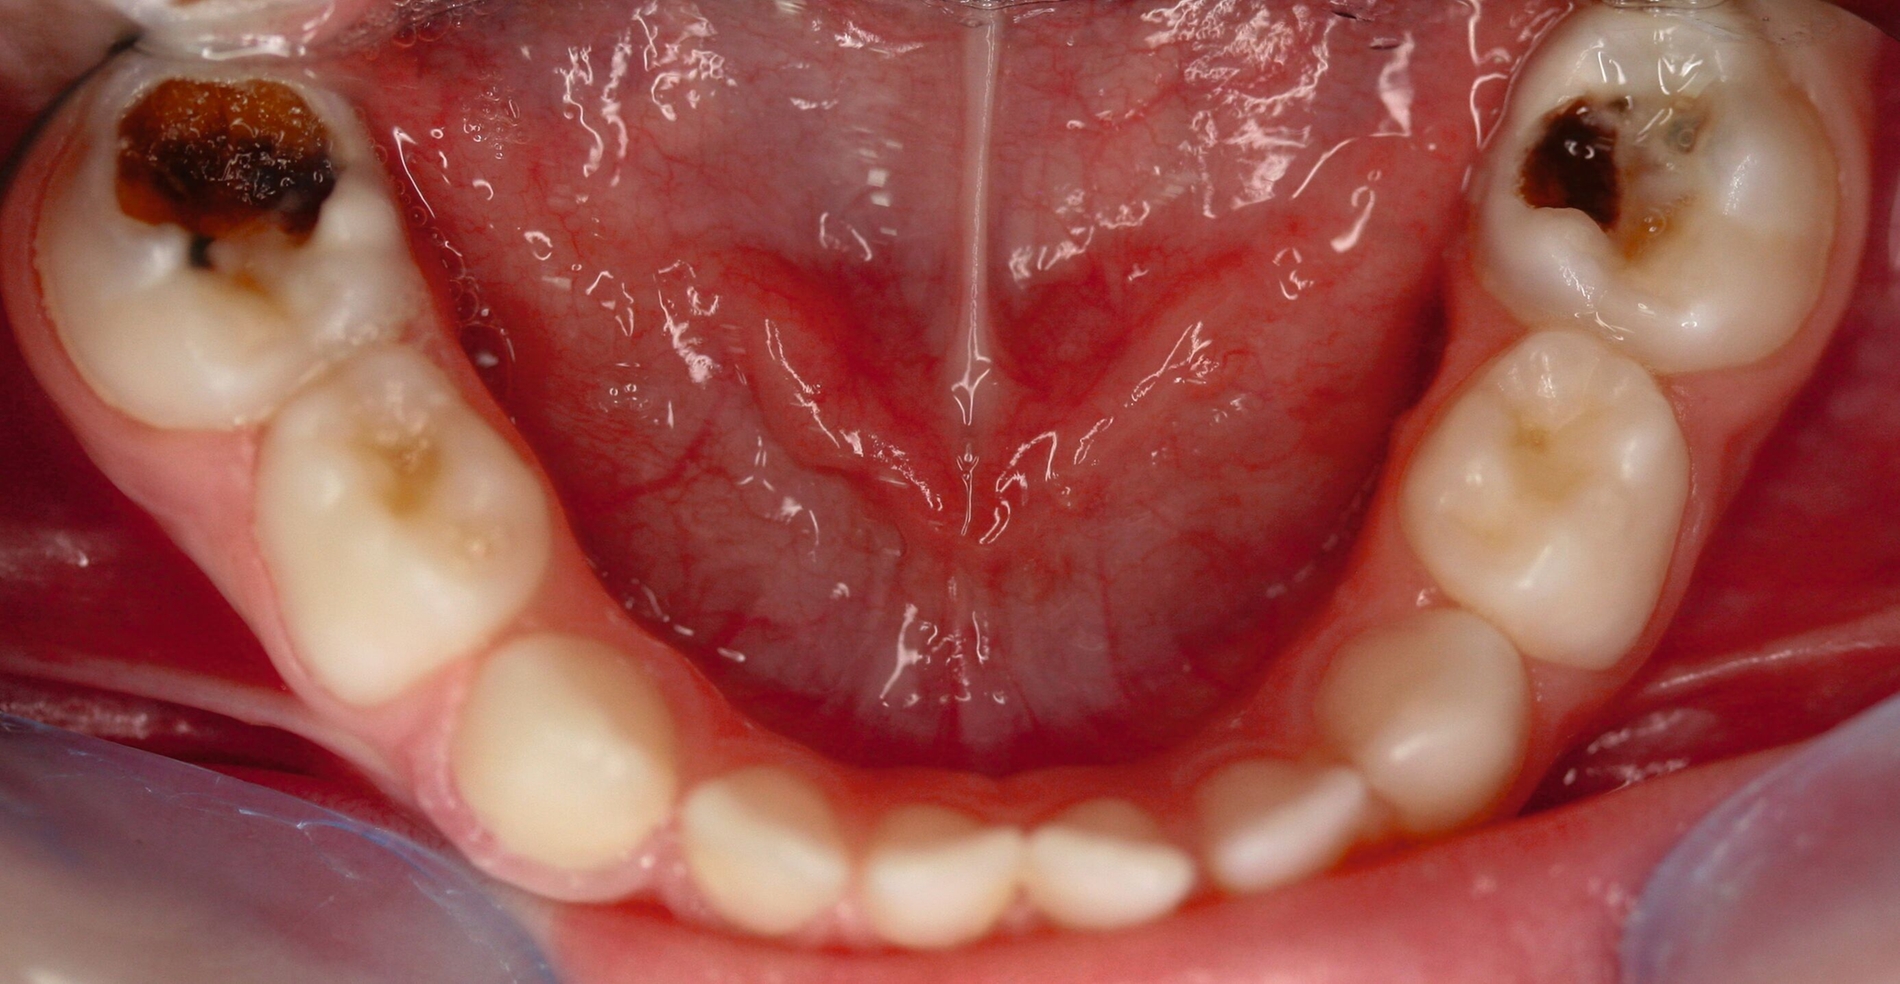

Zentrales Problem bei der Milchgebisskaries ist aber nicht dieser Mineralverlust oder der Defekt, sondern die „übergroße“ Pulpa, die häufig mit betroffen ist (Abbildung 2), bei oftmals zugleich geringer Kooperationswilligkeit oder -fähigkeit der Kinder für invasive Eingriffe. Damit ist bei kariösen Defekten an Milchzähnen die korrekte Diagnose zum Zustand der Pulpa beziehungsweise die Abschätzung der Pulpabeteiligung der kariösen Läsion die primäre und wichtigste Aufgabe. Dies ist allerdings bei Kleinkindern über die Schmerzanamnese und die Röntgenbilder häufig nicht valide möglich. Es gibt zwei Möglichkeiten, dieses Dilemma zu lösen: